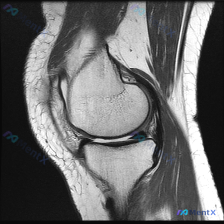

今天遇到一个有意思的读片问题:临床怀疑膝关节软骨异常,但提供的单张矢状位T1加权MRI读下来基本正常,整理一下分析思路和大家分享。

这是一张膝关节矢状位T1加权MRI,图像质量清晰,信噪比良好,可见层面包含股骨远端外侧髁、胫骨近端、后交叉韧带、半月板前后角、髌韧带及Hoffa脂肪垫,整体评估:

- 骨髓: 股骨、胫骨骨髓信号均匀,未见局灶异常信号,骨髓结构正常

- 骨与关节: 骨皮质连续,轮廓规整,无骨质破坏、骨折或大量骨赘;关节间隙宽度正常,无狭窄或力线畸形

- 关节软骨: 股骨髁、胫骨平台软骨厚度可,表面光滑,未见明显剥脱性缺损或软骨下骨囊变,无显著退变征象

- 半月板与韧带: 半月板形态完整,信号均匀,无移位或撕裂征象;后交叉韧带走行自然、连续性好,信号正常

- 软组织: 髌韧带信号正常,Hoffa脂肪垫无异常,关节囊周围无明显肿胀,腘窝无占位

最终这份单张影像的结论是:基本正常的膝关节MRI表现,未见明显急性创伤或显著慢性退行性病变。